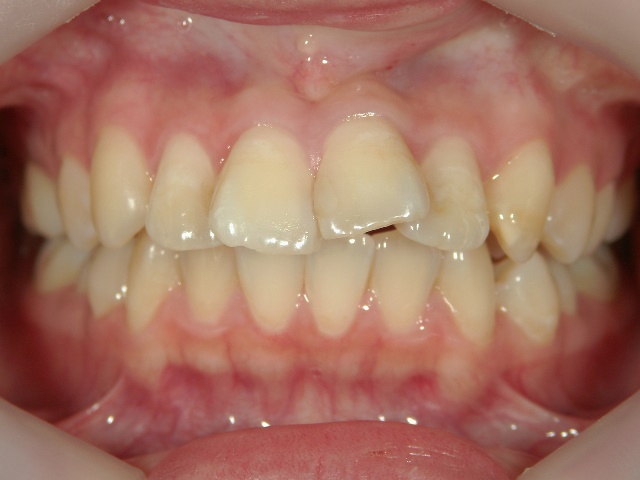

矯正歯科 治療後

no.6_8296_治療後_右.jpgno.6_8296_治療後_正面.jpgno.6_8296_治療後_左.jpg